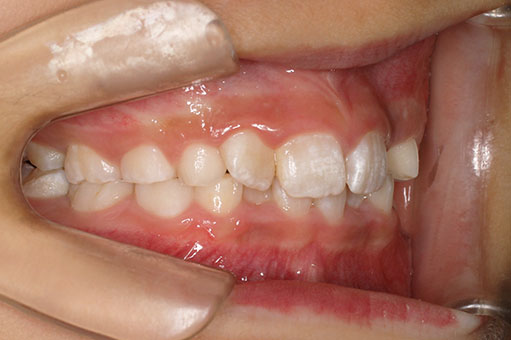

『前歯ががたついて生えてきた』 一般歯科から紹介の患者さんです。 上下4前歯に叢生がみられます。かみ合わせが深く、過蓋咬合。 上顎前歯は舌側傾斜。 永久歯の萌出スペースが上下とも5mmほど足りませんし、 おそらく、これから生えてくる犬歯は八重歯になる状況です。 治療方針としては、小児矯正で叢生(がたつき)を減らし、 永久歯列が生えてから、中学生ごろから本格矯正(マルチブラケット装置)を行います。 十分に側方拡大でスペースを確保し、更に、まだ生えていない永久歯の位置と方向が良ければ、きれいに生えそろうことにより、本格矯正での治療が必要ない場合もありますが頻度的には少ないです。 ある程度はきれいに生えてきても、左右の歯の高さの違いや、歯の回転、角度のズレが残る場合が多いからです。 その多少のがたつきが気にならないのでしたら、小児矯正で終了です。